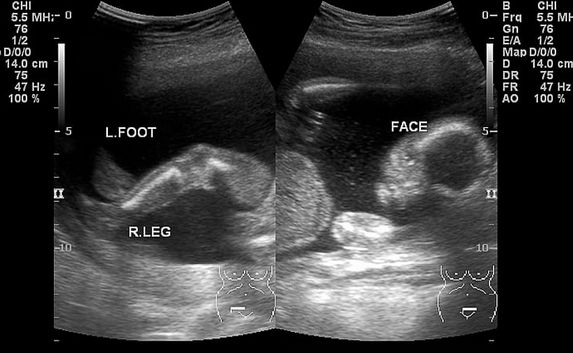

5-8周:超声波(B超)查胎儿心跳及胎囊位置。

21-24周:B超大排畸,是针对胎儿的重大畸形做筛查,如脑部异常、四肢畸形等。这里要说下近些年很流行的四维彩超,价格比普通B超贵了不少,其功能和普通彩超是一样的,很多妈妈做四维彩超的原因大多都是觉得这是宝宝的第一张照片,比较有纪念价值罢了。